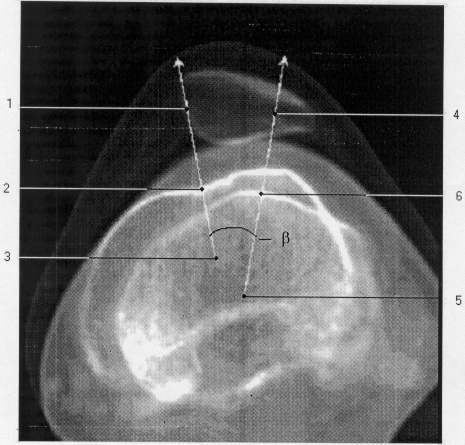

Настоящее изобретение поясняем описанием и прилагаемой копией изображения, полученного путем наложения двух томограмм.

Способ осуществляют следующим образом (см. чертеж).

Для определения угла смещения надколенника и его собственной связки относительно ложа надколенника производят компьютерную томографию коленного сустава. По топограмме устанавливают уровни сканирования: проксимально – вверх от надколенника до 1,5 см, дистально – на уровне бугристости большеберцовой кости. После чего с помощью функции Manipulation Average накладывают томограмму на уровне центральных отделов ложа надколенника и томограмму на уровне прикрепления собственной связки надколенника. Затем на созданном изображении производят две прямые линии:

1 – проведенную через центр ложа надколенника 2 и центр бедренной кости 3, и

4 – проведенную через центр большеберцовой кости 5 и место прикрепления собственной связки надколенника 6.

Измеряют величину смещения надколенника и его собственной связки относительно ложа надколенника, равную углу латерализации собственной связки надколенника, заключенному между прямыми 1 и 4.